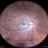

- BRAO, branch retinal artery occlusion

- Scanning laser ophthalmoscope

- Color fundus photograph of a 67 year old male with branch retinal artery occlusion.